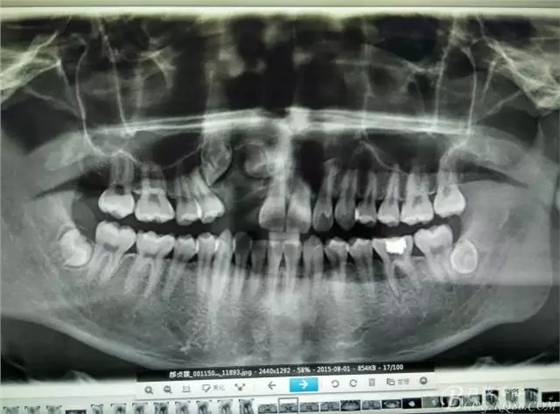

圖18.術(shù)后的全景片檢查:13牙冠與12重疊。11遠中牙根區(qū)好像還有一顆牙齒喲